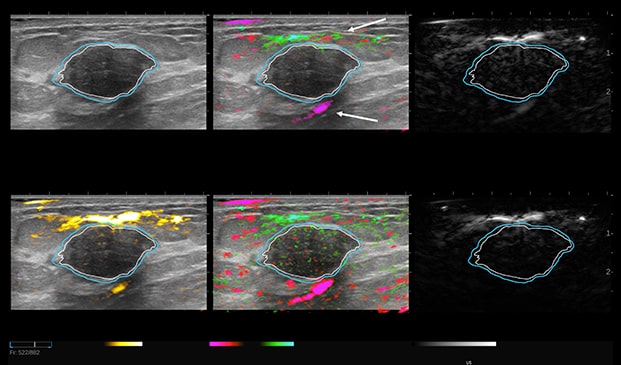

Case Example 2:

48-year-old female, presented with an abnormal mammogram/tomo. 1.9 cm mass seen on ultrasound, negative doppler.

Case Example 2: Observations

Deoxygenated hemoglobin internal to the mass is represented by intense disorganized or polymorphic pink colorization seen on the 6-up image.

These are typical malignant characteristics on OA which are represented on the combined map (upper middle), total hemoglobin (lower left) and relative map (lower middle).

Invasive Ductal Carcinoma Grade III

- ER-

- HER2-

- PR-

- Ki67=80%

The Mass was up-classified to BI-RADS 4C. Biopsy confirmed triple negative cancer. TNC masses typically present with intense deoxygenated mainly internal vessels. Masses with high Ki67 tend to have a lot of internal vessels mainly in the internal and boundary zones, unless there is necrosis.